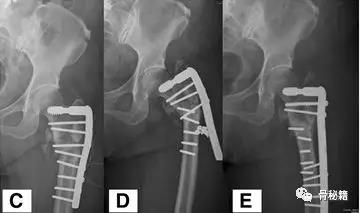

一个双膦酸盐治疗5年的患者粗隆下非典型骨折

采用了髓内钉固定,术后一年内固定失效

更换了DCS+植骨固定,术后四个月又发现了内固定失效再次更换了更长的DCS

这次的固定能成功吗?